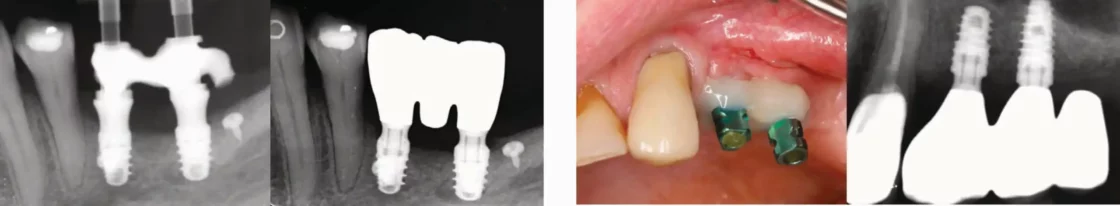

Onnauwkeurige afdrukken in geconnecteerde en verschroefde constructies leiden tot spanning en ook lekkage op botniveau. Extra zorg moet worden besteed aan nauwkeurigheid tijdens het afdrukken.

Voor (grote) bruggen wordt de open tray techniek geadviseerd.

Extra nauwkeurigheid wordt bereikt door de afdrukstiften te splinten met (vloeibaar) composiet. Tandfloss kan worden gebruikt om dit te vergemakkelijken.

Gespalkte open tray afdrukstiften. Gelijke interdentale ruimtes.

Gesplinte gesloten tray afdrukstiften. Gelijke interdentale ruimtes.

Digitale intra-orale scan afdrukken kunnen door stitching van de scanner en het verlijmen op een 3D geprint model minder nauwkeurig zijn. Hoe groter de afstand en de angulatie des te meer dit een rol speelt.

Het is raadzaam om een eenvoudig verificatie gipsmodel te maken met analoge afdrukstiften. Op dit model kunnen dan de Ti-bases verlijmd worden voor het beste resultaat.